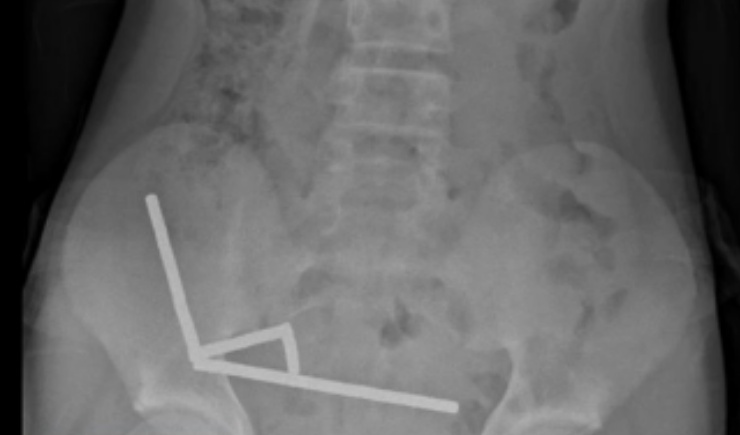

Exames revelaram que os ímãs haviam se agrupado em quatro correntes na parte inferior direita do abdômen, unindo diferentes seções do intestino com sua força magnética, segundo o relatório, que observou que algumas imagens foram distorcidas pelos ímãs. Os médicos então procederam com uma cirurgia exploratória.